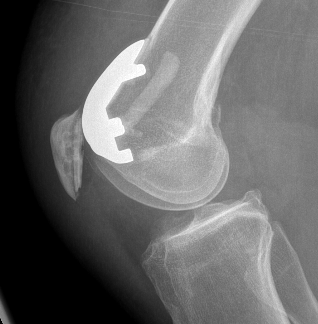

Patellofemoral joint replacement

Technique